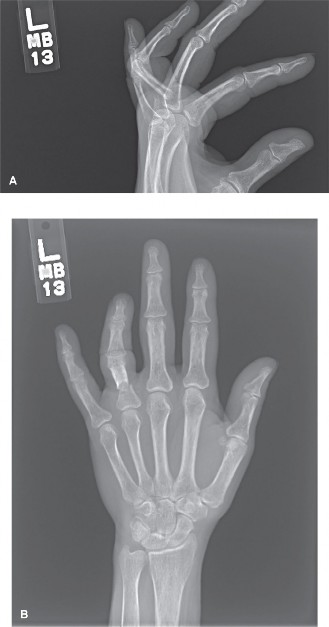

CASE 21 A 22-year-old patient presents after sustaining an injury to her finger…

CASE 37 A 37-year-old, right-hand-dominant male is referred to the emergency de…